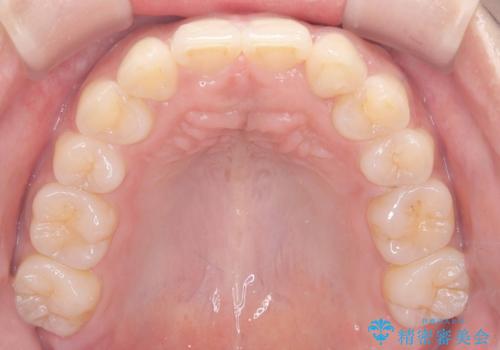

- 「歯の捻じれとがたつき」を主訴に来院された患者様です。

軽度な捻転と叢生だったため、インビザラインのモデレートで治療を行いわずか半年で治療を終える事が出来ました!

目立たないマウスピース矯正【インビザライン】を使用し、

わずか6ヵ月で歯並びがキレイに整いました!

矯正後は、リテーナー(保定装置)を使用し後戻りを防止中です。

患者様にとてもご満足いただけました。